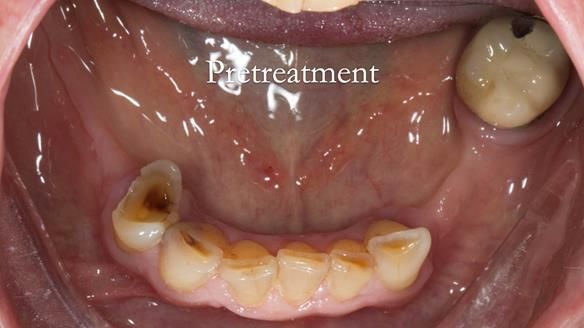

Aesthetically and functionally poor RPDs were replaced for Eileen, a 74 year old woman.

Referred to me by her general dental practitioner specifically for replacement RPDs.

Diagnoses

- Missing teeth in the upper and lower jaws

- Upper and lower metal based RPDs, poorly fitting, worn occlusal surface, reverse curve aesthetics, lacking support

- Poor dental appearance with reverse incisal curve

- Moderate to heavily restored dentition with deep overbite (Class 2 div II)

- Yellowish lower front teeth with small amount of wear.

- The lower right canine (LR3) is worn with MOD cavity.